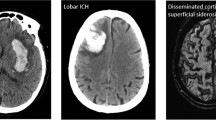

Spontaneous intracerebral hemorrhage (ICH) accounts for 10–15% of all strokes [1] and the worldwide incidence is expected to increase [2, 3]. Patients with ICH are severely affected as one-half dies within 30 days and only 12–39% reach long-term independency [4, 5]. The most important risk factor to develop primary ICH is arterial hypertension, which may lead to vasculopathy of small penetrating arteries located in the basal ganglia and thalamus or brain stem predisposing these regions for hemorrhagic complications [1]. Etiologically different may be lobar ICH, which is more frequently found in the elderly associated with cerebral amyloid angiopathy, characterized by deposition of amyloid-β, micro-hemorrhages, and vascular fragility leading to a greater risk for ICH and recurrence [1]. Anticoagulation-associated ICH has gained importance as the incidence is increasing in conjunction with patients requiring anticoagulation [1]. Important predictors of outcome—ICH volume, neurological status, and age—are non-modifiable; therefore, acute ICH management focusses on prevention and treatment of possibly modifiable factors such as hematoma enlargement (HE), peri-hemorrhagic edema development, acute hydrocephalus with intraventricular hemorrhage, and elevevated intracranial pressure (ICP) to avoid secondary brain injury [6]. Over the last years, several large clinical trials and observational studies provided new evidence, enhancing acute ICH care and improving our understanding of the underlying pathophysiology. In this review, we will outline, discuss, and interpret the latest advances and ongoing investigation.

Clinically significant HE, mostly defined as ICH volume increase of 33%, occurs in about one fourth of spontaneous ICH [19] and in 30–40% in anticoagulation-associated ICH [20••]. HE is one of the most important outcome parameters as it exemplifies a potential therapeutic target [19]. Patients at higher risk for HE may be identified by using contrast-enhanced computed tomography (CT) to depict the so-called spot sign; spot sign-positive patients showed a HE rate of 54.1% compared to 18.6% (spot sign negative) resulting in a negative predictive value of 78% (71–84) [21]. Recently, various other non-contrast CT parameters have been assessed for HE prediction, i.e., blend sign, fluid level, intrahematoma hypodensities, black hole sign, swirl sign, heterogeneous hematoma density, or irregular shape of ICH [22] (please see Fig. 1). Easily assessable parameters have been condensed to calculate a 5-point prediction score (BAT score: 1 point for blend sign, 2 points for any intrahematoma hypodensity, and 2 points for timing of CT scan < 2.5 h) which identified subjects at high risk of HE with good accuracy (AUC 0.65–0.70) and a BAT score ≥ 3 showed almost 90% specificity [23]. Another HE prediction model, the so-called BRAIN-Score, was developed from trial data (INTERACT-1 and INTERACT-2) also integrating clinical information (prior anticoagulation) and notably weighing time from symptom onset to diagnosis [24]. HE is caused by active bleeding during the hyper-acute phase; hence, knowledge of the time window is important as HE-limiting treatment shows greater potential the earlier applied [6]. Nevertheless, HE may occur protractedly up to 24 h or even longer (24–48 h) especially in patients with disturbed hemostasis, largely due to anticoagulation [25, 26]. Therefore, the two main therapeutic interventions to minimize HE constitute aggressive blood pressure and hemostatic management, which will be discussed in the following.